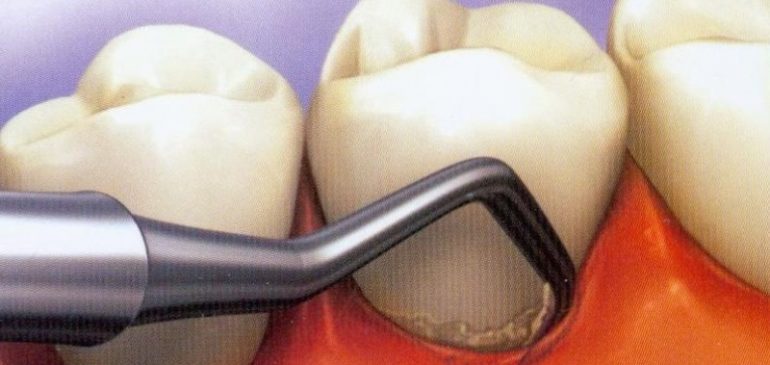

Chiuretaj subgingival

Chiuretajul subgingival este o procedura periodontica prin care se curata santul subgingival cu ajutorul chiuretei, pentru a indeparta tartrul si placa bacteriana, precum si tesutul afectat de acestea – tesut de granulatie, cu scopul de a realiza reatasarea gingiei de dinte. Interventia este mai ampla, deoarece implica efectuarea anesteziei, dezgolirea chirurgicala a radacinii dintilor si prescrierea unui tratament antibiotic.

Chiuretajul subgingival este o procedura de baza in tratamentul pungilor gingivale si se poate executa ca atare sau dupa ce s-a efectuat planarea radiculara. Aceasta interventie este recomandata pentru pungi parodontale cu adancimea de 4 – 6 mm, nefiind eficienta pentru adancimi mai mari.

Chiuretele sunt esentiale pentru succesul acestei interventii; acestea trebuie sa fie foarte bine ascutite si sa fie manuite cu dexteritate. Pentru netezirea radacinei dintelui se introduce chiureta in santul gingival, urmarind curbura radacinii cu ajutorul curburii chiuretei. La capatul santului se roteste chiureta astfel incat manerul sa fie paralel cu suprafata radacinii si se trage in afara. Se actioneaza doar prin miscari de tragere. Pentru o curatare adecvata sunt necesare mai multe tipuri de chiurete. Se fac spalaturi cu ser fiziologic sau solutie de clorhexidina.

Exista doua tipuri de chiuretaj subgingival: inchis si deschis. Chiuretajul in camp inchis se efectueaza fara a decola gingia, iar chiuretajul in camp deschis (operatie cu lambou) se efectueaza prin incizia cu bisturiul a papilelor interdentare pana la osul alveolar, urmata de indepartarea tesutului epitelial inflamat si necrozat. Chiuretajul in camp deschis ofera o vizibilitate mai buna este indicat pentru pungile parodontale mai adanci.